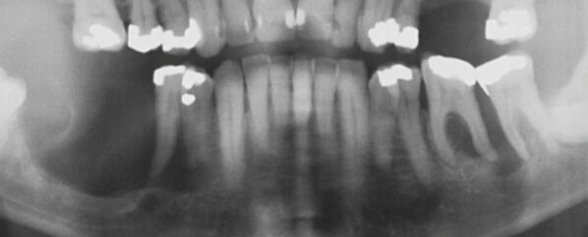

multiple myeloma

-

骨破壞

-

蛋白尿

-

punched out

-

Plasma cell 大小不一

-

κ chain 超多 (10:1) → 來自單株

-

可能表現 CD79a, CD56